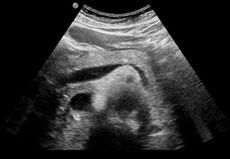

Von der Krebsvorsorge und -nachsorge bis zum Gallensteinleiden: Die Ultraschalluntersuchung (Sonografie) ist eine schmerzfreie Methode zur Kontrolle der inneren Organe. Dabei werden die Strukturen des Körpers durch Ultraschallwellen bildlich dargestellt.

Wir bieten folgende Ultraschalluntersuchungen an:

Abdomen (Bauchorgane wie Leber, Galle, Bauchspeicheldrüse, Nieren, Milz, Darm...) incl. der Bauchgefäße